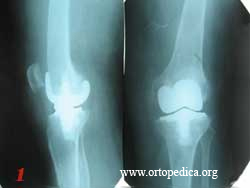

3. Состояние после ревизионного эндопротезирования